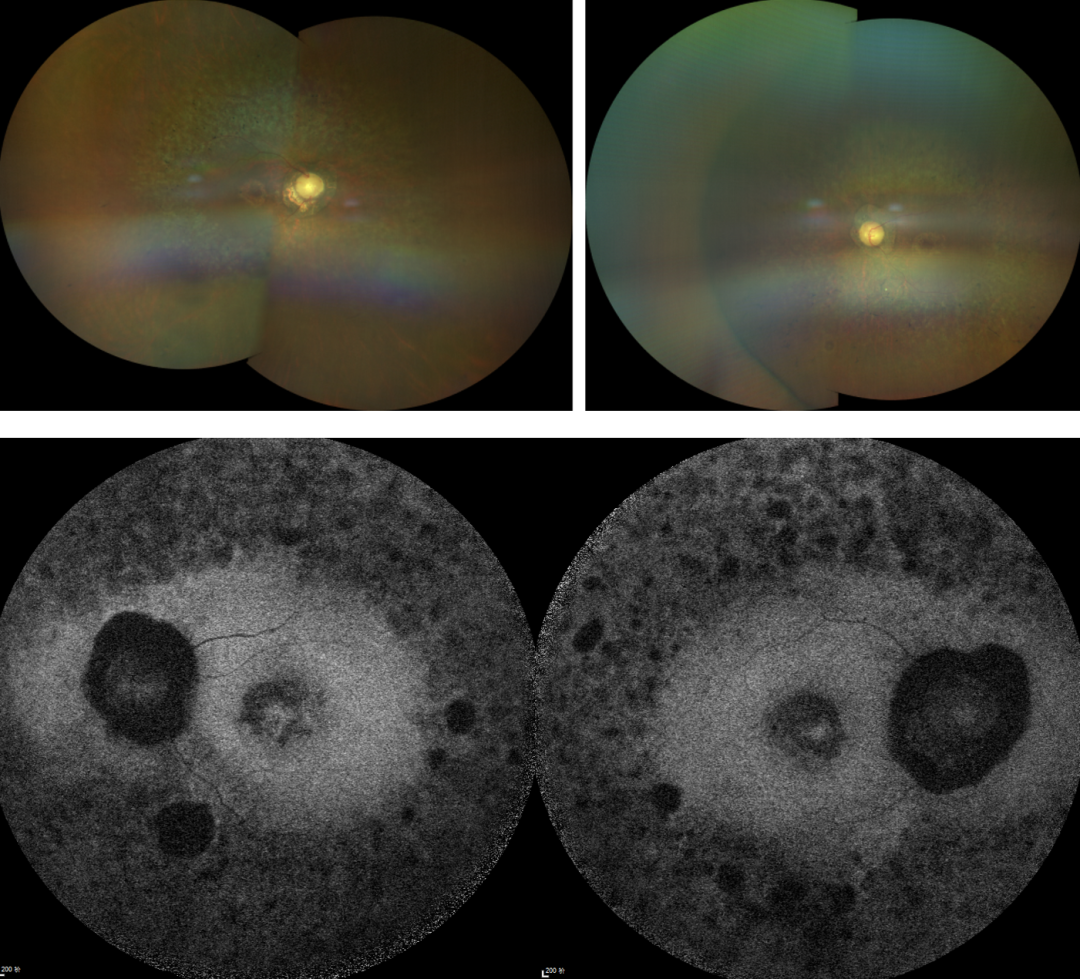

RP的診斷主要依靠眼底檢查、視野檢查、視網(wǎng)膜電圖(ERG)和基因檢測。眼底檢查可見典型的"骨細胞樣"色素沉著,ERG顯示視網(wǎng)膜功能下降,基因檢測可確定具體的突變基因。

視網(wǎng)膜色素變性